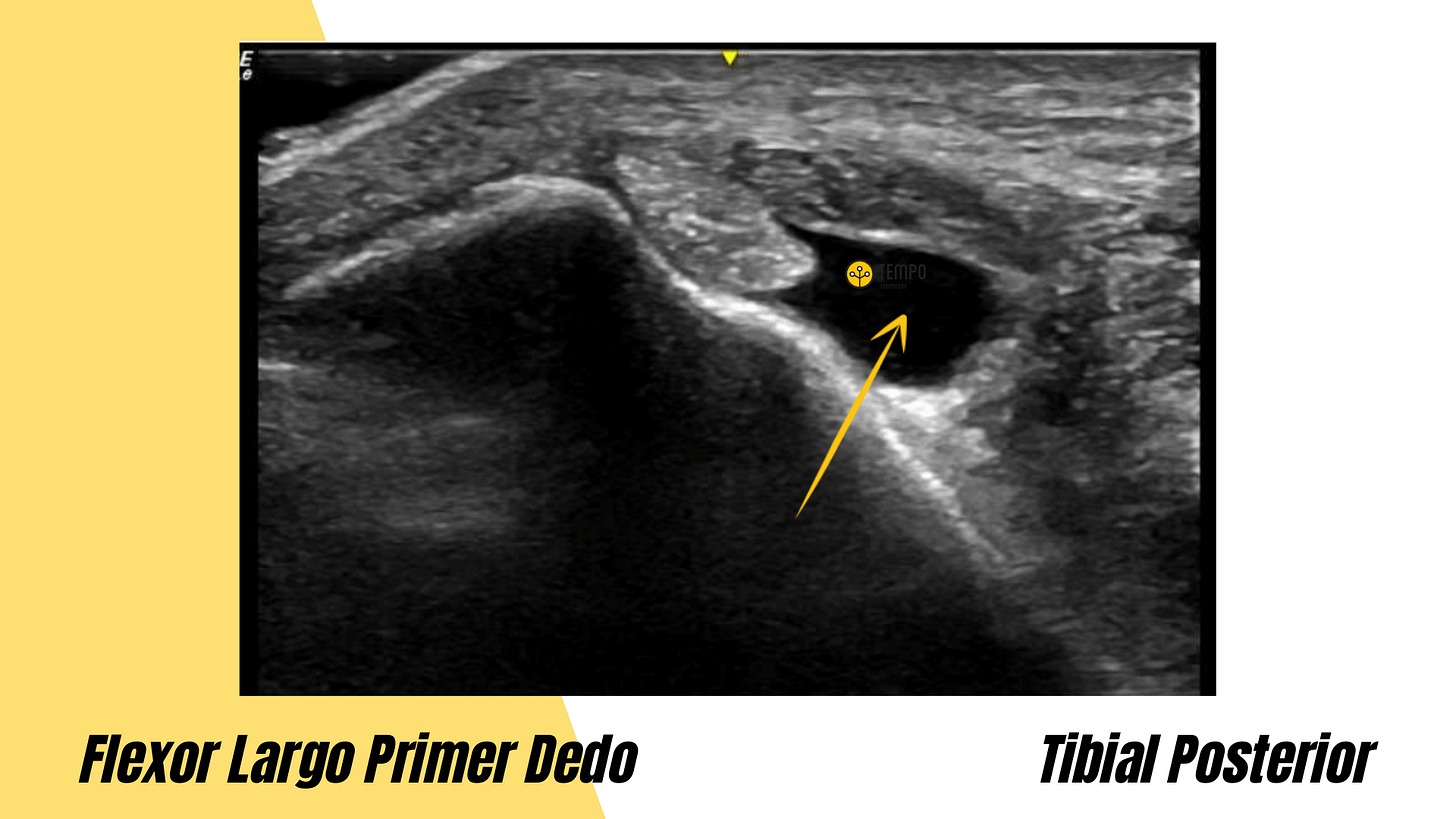

3. ¿A qué tendón pertenece este exceso de líquido?

3. Respuesta correcta: Tibial Posterior.

Es el primer tendón del compartimento medial del tobillo.